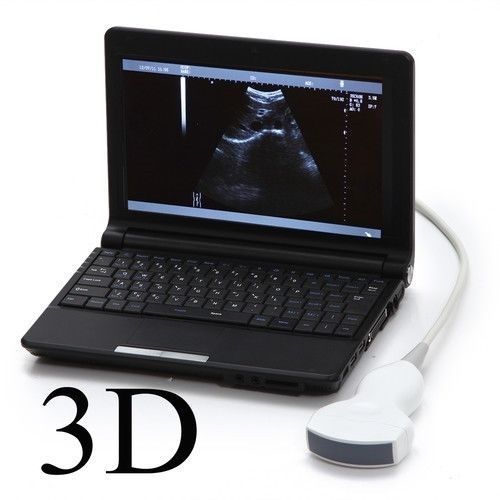

DIAGNOSTIC ULTRASOUND MACHINES FOR SALE

Laptop Ultrasound Machine, Notebook Digital Ultrasound scanner, 3.5 Convex probe

Sale price$ 1,648.00

Regular price$ 1,758.00